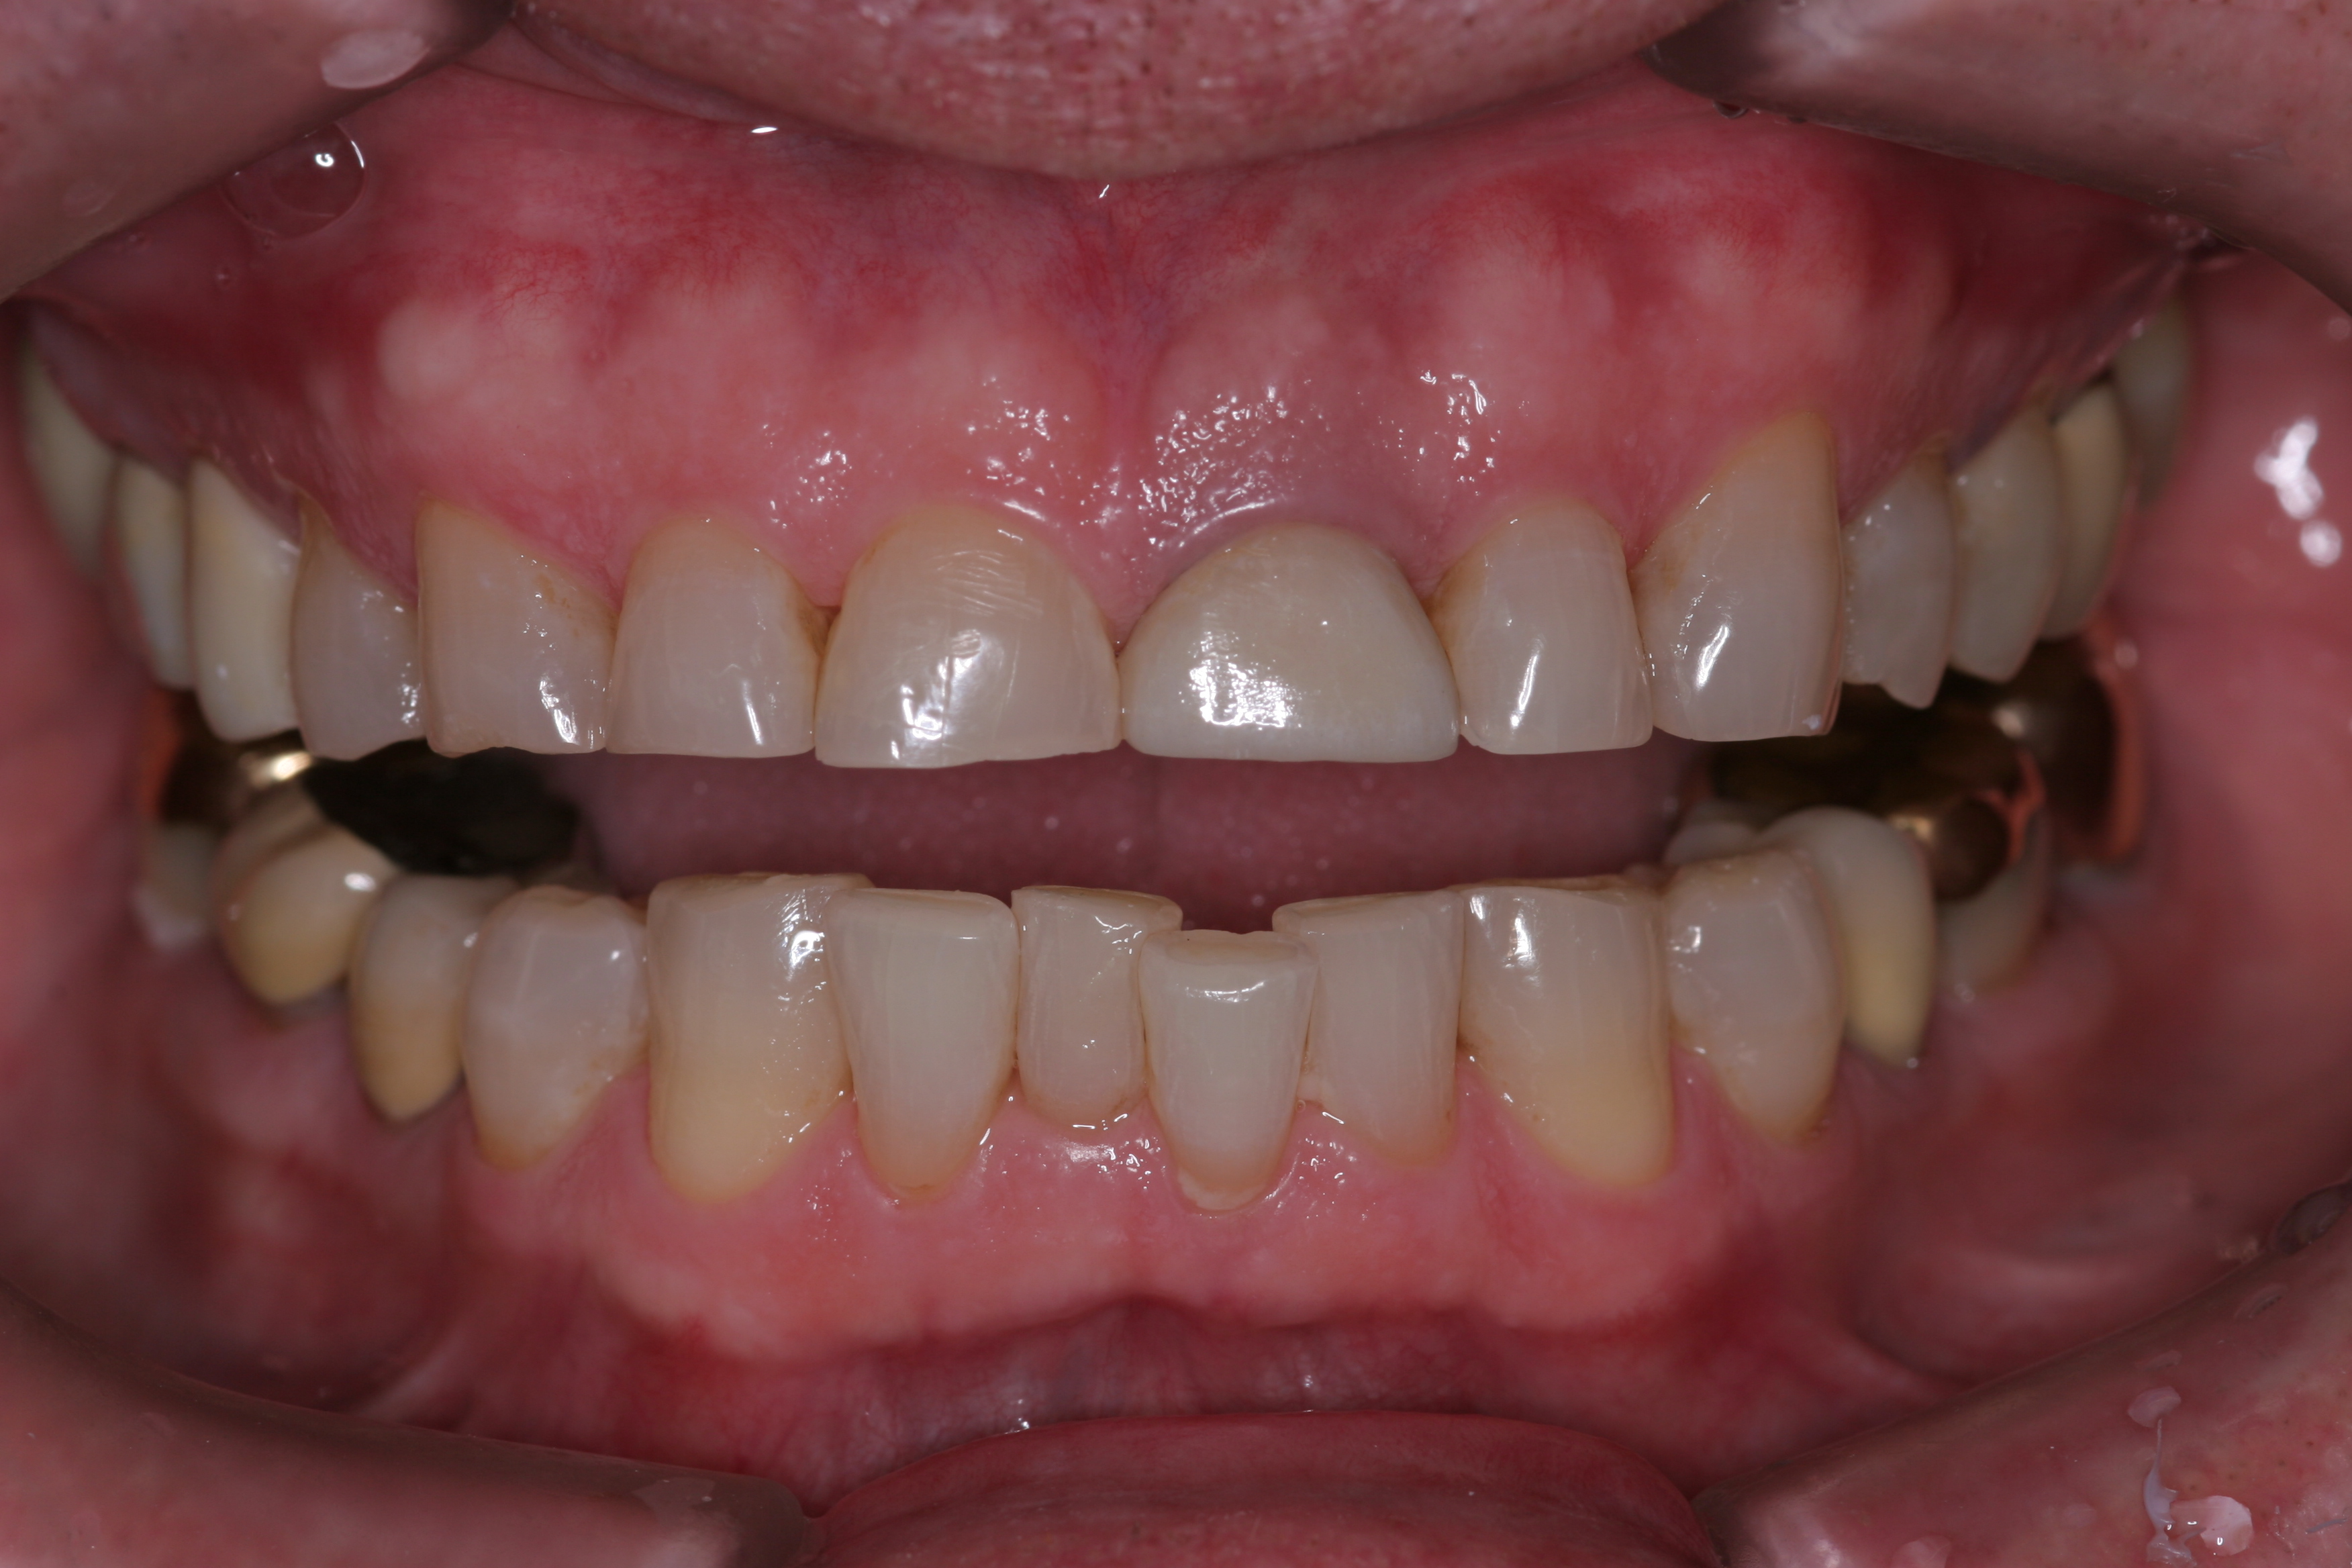

Treatment for this patient included posterior reductive equilibration and additive anterior equilibration (restoration) to eliminate the CR/MIP interferences and to meet the requirements of occlusal stability. Teeth Nos. 5 through 11 and 22 through 27 were prepared for full-coverage lithium-disilicate restorations. Crestal bone heights were evaluated. Soft-tissue crown lengthening was performed on the maxillary anterior teeth by a soft-tissue diode as needed. The esthetic, functional, and phonetic changes were evaluated and confirmed in the provisional restorative phase (Figure 17 through Figure 21).

(17.) The esthetic, functional, and phonetic changes were evaluated and confirmed in the provisional restorative phase.

Figure 17

(18.) The provisional restorations show the vertical and horizontal changes in the incisal edge position.

Figure 18

(19.) The provisional restorations show the vertical and horizontal changes in the incisal edge position.

Figure 19

(20.) The provisional restorations show the vertical and horizontal changes in the incisal edge position.

Figure 20

(21.) The provisional restorations show the vertical and horizontal changes in the incisal edge position.

Figure 21